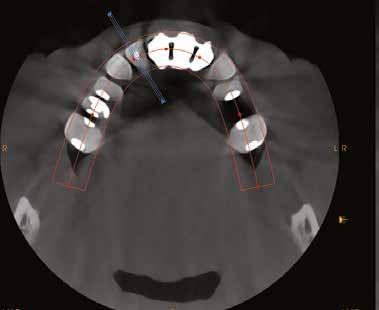

A 62 éves férfi páciens ajánlás útján érkezett rendelőnkbe. Négy felső metszőfogával voltak panaszai, amelyek egy 30 évvel korábbi balesetből kifolyóan gyökérkezelésen, illetve különböző protetikai beavatkozásokon estek át. Mind a négy fog panaszos volt, a 2.1-es fognál mobilitást tapasztaltunk, amelyet a páciens is megerősített (1. a–b ábra)

Először egy Cone Beam CT-felvétel (CBCT) készült a felső fogívről, amelyen látszott a 1.2–2.2 fogak periapikális gyulladása (2–3. ábra) . Ezenfelül a 2.1-es fog bukkális oldalán kiterjedt csonthiány, valamint a gyökércsúcs felett egy kis darab amalgám is látható volt, amely feltehetően a 2.1-es fogból származott. A felvételek alapos elemzését követően úgy döntöttünk, hogy a kezelés során eltávolítjuk a 1.2–2.2-es fogakat és alveolus prezervációt végzünk, hogy minimalizáljuk a fogeltávolítás következtében fellépő csonthiányt.

3. ábra: Kiindulási CBCT, a 21-es fognál koronális nézetből jól látszik a bukkális csonthiány. – 4. a–c. ábra: A kiindulási állapotról készült digitális lenyomatok.

8. a–b. ábra: A fogeltávolítást követően készült digitális lenyomatok. – 9. ábra: A négy lehetséges implantátumpozíció elemzése.

10. ábra: Végső tervezés: a két implantátum pozíciójának meghatározása a CBCT és a digitális lenyomatok egymásra vetítésével.

11. a–c ábra: Az implantátumok pozicionálása és a sebészi sablon megtervezése. – 12. ábra: Kontrollröntgen a behelyezett implantátumokról.